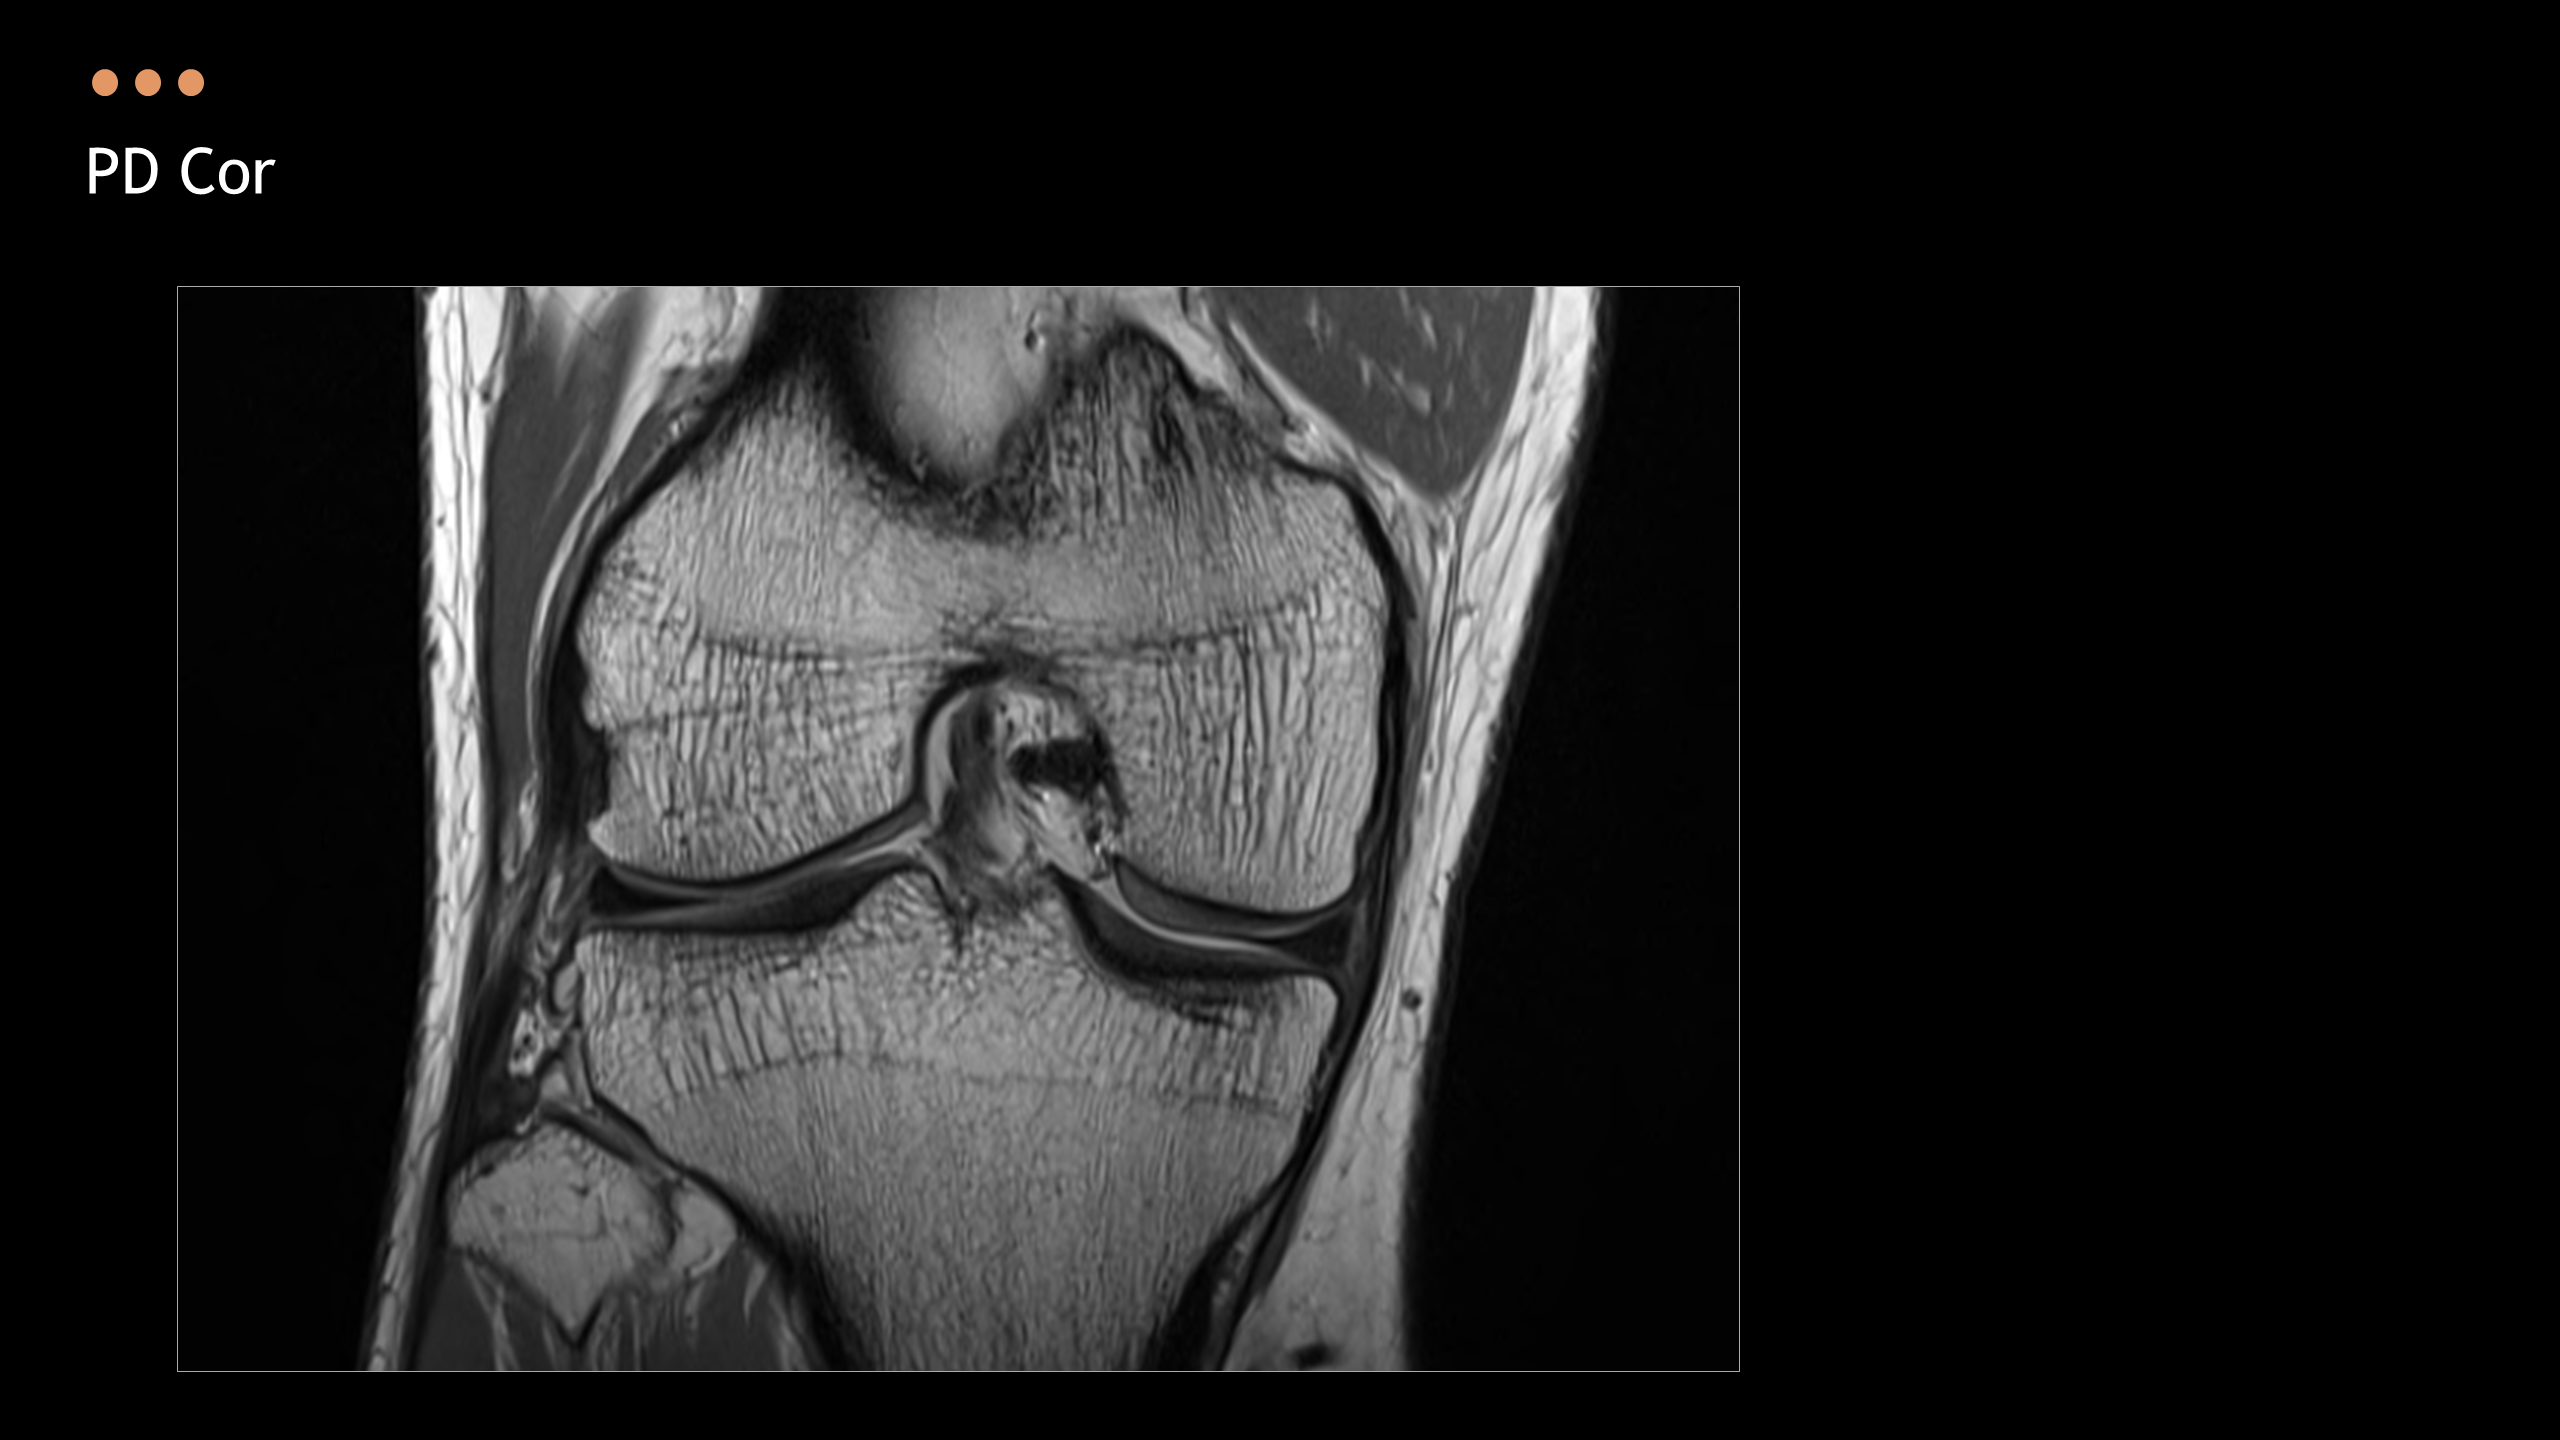

주제: The Knee MRI Approach

강사: 신민섭

아래의 Normal Knee MR Anatomy를 숙지하고 오셔야, 강의에 어려움이 없습니다.